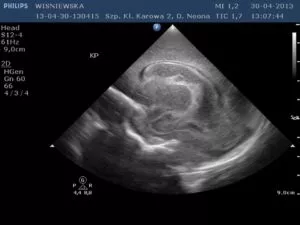

Jeżeli krwawienie zlokalizowane jest tylko w macierzy rozrodczej to według obowiązującej klasyfikacji w modyfikacji Papilla, jest to krwawienie I stopnia. (ryc. 1). Gdy krew przedostanie się do światła komór bocznych mózgu, w zależności od ich wypełnienia, mówimy o krwawieniu II stopnia (10-20% objętości komór) (ryc. 2) lub krwawieniu III stopnia (powyżej 50% objętości komór bocznych). (ryc.3). Najcięższą postacią krwawienia do OUN jest krwawienie do okołokomorowego miąższu mózgu i nazywane jest zawałem żylnym krwotocznym przykomorowym.

Ryc. 3 Krwawienie III stopnia